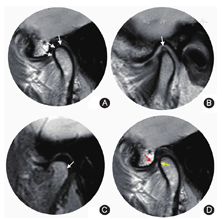

①按移位层面分为正常上位(关节盘后带后缘位于髁突上方12点的位置,即"盘-突12点")(图2A)、部分移位(部分层面移位)、完全移位(所有层面均移位)[3,9];②按移位方向分为前移位、后移位、内侧移位及外侧移位,关节盘后带后缘的切线与经过髁突12点方向的垂线前后夹角超过10°为前移位(图2B),关节盘内缘或外缘超过经髁突内外极连线长轴的垂线为侧方移位(图2C);③按前移位程度分为正常上位(0~10°)、轻微前移位(11~30°)、轻度前移位(31~50°)、中度前移位(51~80°)、重度移位(>80°)[10,11];④按张口位关节盘是否恢复正常位置分为可复性移位或不可复性移位。